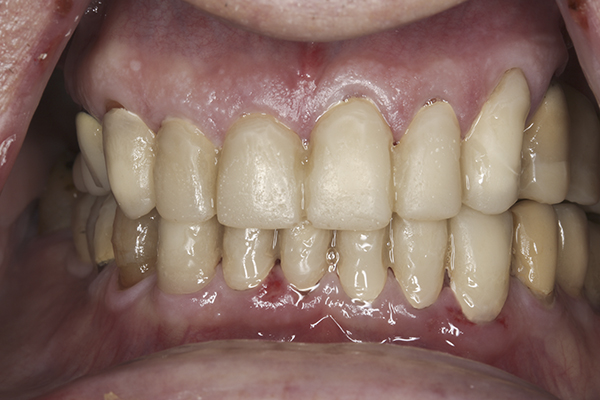

(24.) Provisionals, anterior, closed view.

Figure 24

(25.) Provisionals, left lateral, closed view.

Figure 25